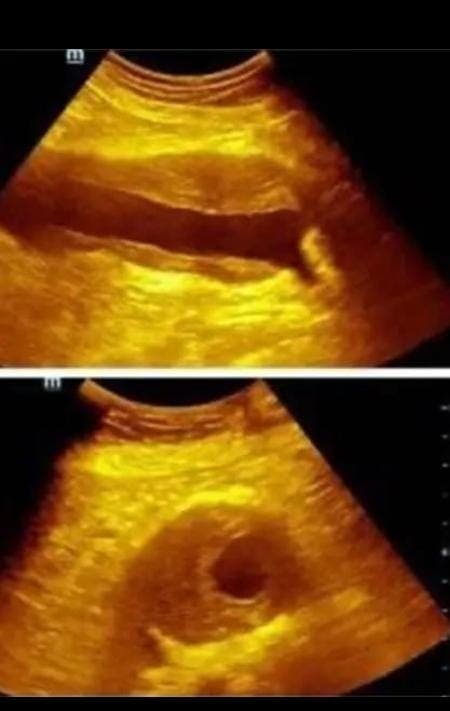

O diagnóstico precoce é crucial e pode ser realizado através de exames de imagem como ultrassonografia, tomografia computadorizada ou ressonância magnética. Exames preventivos são recomendados para pessoas com fatores de risco. O tratamento varia de acordo com a gravidade e o tamanho do aneurisma, podendo incluir monitoramento médico, medicamentos para controlar a pressão arterial ou cirurgia.